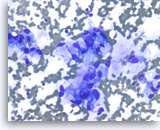

Ductal adenocarcinoma #1,

Pancreas FNA, Direct Smear.

The tumor cells have prominent intracytoplasmic vacuoles, irregular nuclear contours, vesicular chromatin and are arranged in three-dimensional clusters.

40X

Ductal adenocarcinoma #1,

Pancreas FNA, Direct Smear.

The tumor cells have prominent intracytoplasmic vacuoles, irregular nuclear contours, vesicular chromatin and are arranged in three-dimensional clusters.

40X